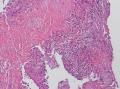

气管镜活检

性别年龄60临床诊断肺结核

标本名称气管镜活检

• 气管镜活检图2

图2

考虑炎性病变,结核可能?

考虑鳞癌,进一步检查。

支气管粘膜炎症,伴有出血、渗出、坏死及少许肉芽组织,诊断结核证据不足!

考虑炎症

炎性病变

出血及坏死,有肉芽性炎,结核还是要考虑的,多做些工作,逐一排除

出血及坏死,有肉芽性炎,结核还是要考虑的,多做些工作,逐一排除,首先考虑结核。